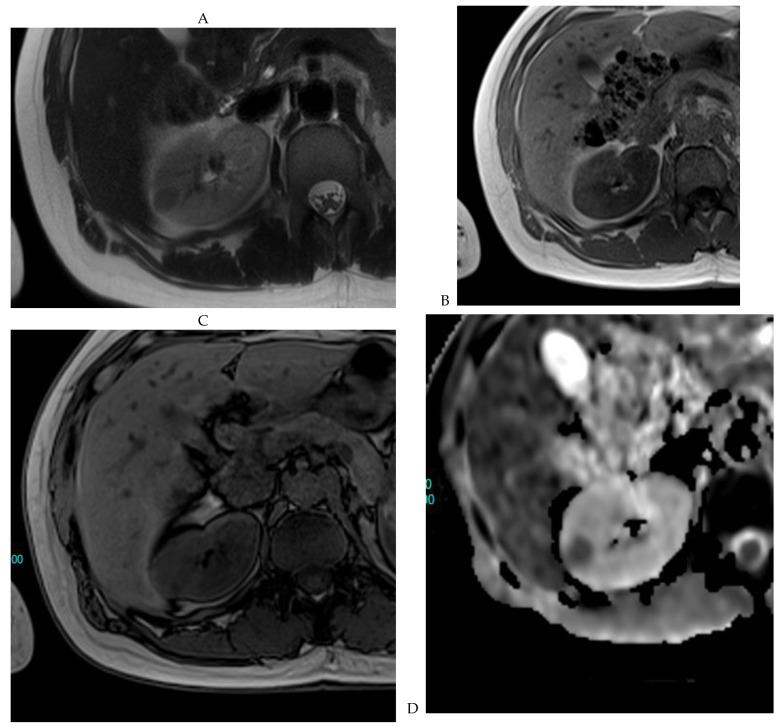

This review highlights recent advances in renal cell carcinoma (RCC) imaging. It begins with dual-energy computed tomography (DECT), which has demonstrated a high diagnostic accuracy in the evaluation of renal masses. Several studies have suggested the potential benefits of iodine quantification, particularly for distinguishing low-attenuation, true enhancing solid masses from hyperdense cysts. By determining whether or not a renal mass is present, DECT could avoid the need for additional imaging studies, thereby reducing healthcare costs. DECT can also provide virtual unenhanced images, helping to reduce radiation exposure. The review then provides an update focusing on the advantages of multiparametric magnetic resonance (MR) imaging performance in the histological subtyping of RCC and in the differentiation of benign from malignant renal masses. A proposed standardized stepwise reading of images helps to identify clear cell RCC and papillary RCC with a high accuracy. Contrast-enhanced ultrasound may represent a promising diagnostic tool for the characterization of solid and cystic renal masses. Several combined pharmaceutical imaging strategies using both sestamibi and PSMA offer new opportunities in the diagnosis and staging of RCC, but their role in risk stratification needs to be evaluated. Although radiomics and tumor texture analysis are hampered by poor reproducibility and need standardization, they show promise in identifying new biomarkers for predicting tumor histology, clinical outcomes, overall survival, and the response to therapy. They have a wide range of potential applications but are still in the research phase. Artificial intelligence (AI) has shown encouraging results in tumor classification, grade, and prognosis. It is expected to play an important role in assessing the treatment response and advancing personalized medicine. The review then focuses on recently updated algorithms and guidelines. The Bosniak classification version 2019 incorporates MRI, precisely defines previously vague imaging terms, and allows a greater proportion of masses to be placed in lower-risk classes. Recent studies have reported an improved specificity of the higher-risk categories and better inter-reader agreement. The clear cell likelihood score, which adds standardization to the characterization of solid renal masses on MRI, has been validated in recent studies with high interobserver agreement. Finally, the review discusses the key imaging implications of the 2017 AUA guidelines for renal masses and localized renal cancer.

本综述重点介绍了肾细胞癌(RCC)成像的最新进展。首先是双能计算机断层扫描(DECT),它在评估肾肿块方面已显示出较高的诊断准确性。多项研究表明碘定量具有潜在益处,特别是在区分低衰减、真正强化的实性肿块与高密度囊肿方面。通过确定是否存在肾肿块,DECT可以避免进行额外的影像学检查,从而降低医疗成本。DECT还可以提供虚拟平扫图像,有助于减少辐射暴露。该综述接着介绍了最新进展,重点是多参数磁共振(MR)成像在RCC组织学亚型分类以及肾良性与恶性肿块鉴别方面的优势。一种提议的标准化图像逐步解读方法有助于高精度地识别透明细胞RCC和乳头状RCC。对比增强超声可能是一种用于实性和囊性肾肿块特征化的有前景的诊断工具。几种同时使用锝[99mTc]甲氧基异丁基异腈(sestamibi)和前列腺特异性膜抗原(PSMA)的联合药物成像策略为RCC的诊断和分期提供了新机会,但其在风险分层中的作用有待评估。尽管放射组学和肿瘤纹理分析因可重复性差且需要标准化而受到阻碍,但它们在识别预测肿瘤组织学、临床结果、总生存期和治疗反应的新生物标志物方面显示出前景。它们有广泛的潜在应用,但仍处于研究阶段。人工智能(AI)在肿瘤分类、分级和预后方面已取得令人鼓舞的结果。预计其在评估治疗反应和推进个性化医疗方面将发挥重要作用。该综述接着重点介绍了最近更新的算法和指南。2019年版的博斯尼亚克分类纳入了MRI,精确定义了以前模糊的影像学术语,并允许将更大比例的肿块归类为低风险类别。最近的研究报告称,高风险类别的特异性有所提高,阅片者之间的一致性也更好。透明细胞可能性评分在MRI上对实性肾肿块的特征化增加了标准化,最近的研究已验证其具有较高的观察者间一致性。最后,该综述讨论了2017年美国泌尿协会(AUA)肾肿块和局限性肾癌指南的关键影像学意义。